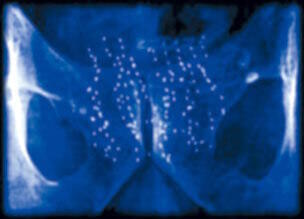

Stephen Cherniske : Les études sur l'homme ne montrent aucune corrélation entre la DHEA ou la testostérone et le cancer de la prostate. Des études in vitro montrent que la DHEA inhibe en fait le cancer de la prostate et même, donner à des animaux des quantités massives de DHEA n'induit pas de croissance anormale de la prostate. Une étude publiée dans le Journal Cancer research conclut : |

| Naysayer : Mais j'ai lu dans des douzaines d'articles que la DHEA pourrait causer le cancer de la prostate. Tous ces articles ne peuvent être faux.

Stephen Cherniske : Bien sûr qu'ils le peuvent. Les journalistes ne sont pas des scientifiques. S'ils pensent que leurs sources sont exactes, ils impriment l'information sans vérifier dans la littérature médicale. Ensuite, l'histoire est répétée et, comme vous le savez, si une erreur est suffisamment répétée, elle finit par paraître vraie. Si les journalistes voulaient ou étaient capables de faire une recherche méticuleuse sur ce sujet, ils trouveraient une étude animale rapportée dans le European Journal of Urology qui conclut : |

|

«La DHEA et l'acide 9-cis-rétinoïque sont les agents [anticancéreux] les plus actifs identifiés à ce jour. La DHEA inhibe l'induction du cancer de la prostate lorsqu'elle est administrée régulièrement avant une exposition à un carcinogène et lorsque son administration est retardée jusqu'à ce que les lésions prénéoplasiques de la prostate apparaissent28.» |

Stephen Cherniske : Et les études animales sont utilisées systématiquement pour établir la sécurité et l'efficacité, plus particulièrement lorsqu'il n'y a aucune preuve que la DHEA puisse causer ou accélérer chez l'homme une croissance anormale de la prostate. |

Stephen Cherniske : Non, il n'y a que des déductions, des spéculations. Regardez, si la DHEA causait une croissance anormale de la prostate, des niveaux élevés de DHEA seraient associés à des scores élevés de PSA. En fait, chez l'homme, de faibles niveaux de DHEA sont associés à des niveaux élevés de PSA et l'inverse est également vrai. Des hommes avec des niveaux élevés de DHEA ont de faibles scores de PSA. |

| Naysayer : Quand même, des suppléments de DHEA pourraient augmenter les niveaux de PSA.

Stephen Cherniske : Cela ne se produit pas. Étude après étude, la supplémentation avec de la DHEA - même à doses élevées - n'a pas montré d'effet négatif sur les niveaux de PSA. Dans une communication privée, de nombreux cliniciens m'ont dit qu'ils ont observé un déclin progressif des niveaux de PSA chez des patients prenant de la DHEA. C'est cohérent avec ces résultats récents montrant que des patients atteints d'un cancer de la prostate ont des niveaux sériques élevés de glucocorticoïdes immunosuppresseurs et que les métabolites de DHEA peuvent inhiber l'expression de la PSA en interrompant la liaison de l'androgène avec le récepteur androgénique de la prostate29. Cela apporte encore plus de preuves que la DHEA peut en fait réduire le risque de cancer de la prostate. |

Stephen Cherniske : En fait, la Division de prévention du cancer de l'Institut national du cancer a planifié une étude de supplémentation en DHEA comme moyen de prévenir le cancer de la prostate chez l'homme. |